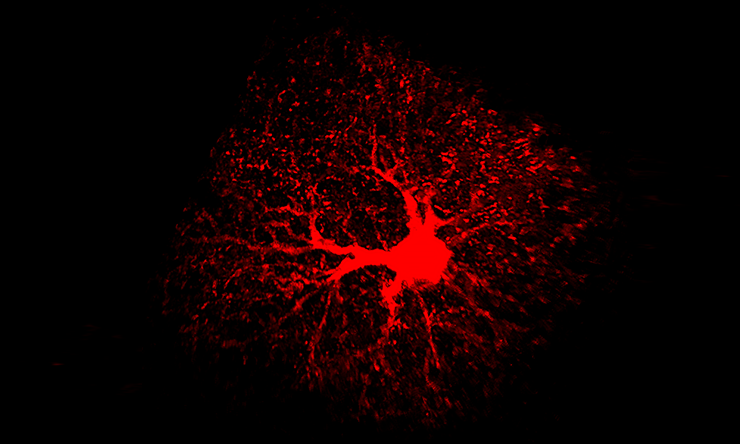

Adult astrocytes key to learning, memory

Researchers at Baylor College of Medicine reveal that astrocytes, the most abundant cells in the brain, play a direct role in the regulation of neuronal circuits involved in learning and memory. The findings appear in the journal Neuron.

“We found that NFIA-deficient astrocytes presented defective shapes and altered functions,” said Deneen, who holds the Dr. Russell J. and Marian K. Blattner Chair and is a member of the Dan L Duncan Comprehensive Cancer Center at Baylor. “Surprisingly, although the NFIA gene was eliminated in all brain regions, only the astrocytes in the hippocampus were severely altered. Other regions, such as the cortex and the brain stem, were not affected.”

Astrocytes in the hippocampus also had less calcium activity – calcium is an indicator of astrocyte function – as well as a reduced ability to detect neurotransmitters released from neurons. NFIA-deficient astrocytes also were not as closely associated with neurons as normal astrocytes.